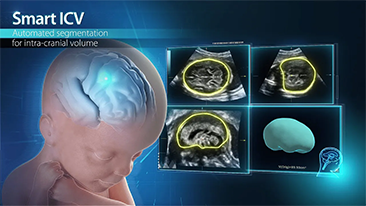

AlimentÊe par la plateforme avancÊe ZST+, la gamme complète de solutions intelligentes Nuewa est con?ue spÊcialement pour amÊliorer la santÊ des femmes avant, pendant et après la grossesse, de manière à poser des diagnostics complets et efficaces pour rÊpondre à des dÊfis cliniques de plus en plus exigeants.